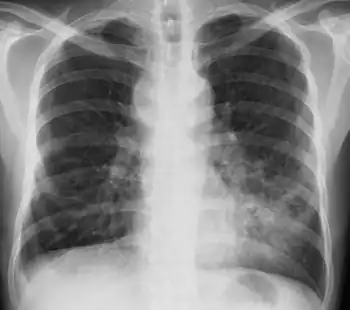

| CT scan of patient with right middle lobe aspiration and Mycobacterium avium infection consistent with Lady Windermere syndrome | |